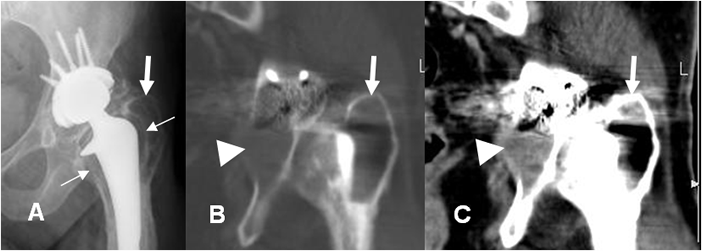

Fig 126 D. Granulomatosis agresiva.

A: TAC axial en ventana de tejido y B: TAC axial en ventana de hueso. Igual paciente anterior. Osteolisis en el trocánter mayor (Flecha gruesa) y otra lesión osteolítica con masa de tejidos blandos, en el ramo isquiopúbico. (Flechas delgadas).